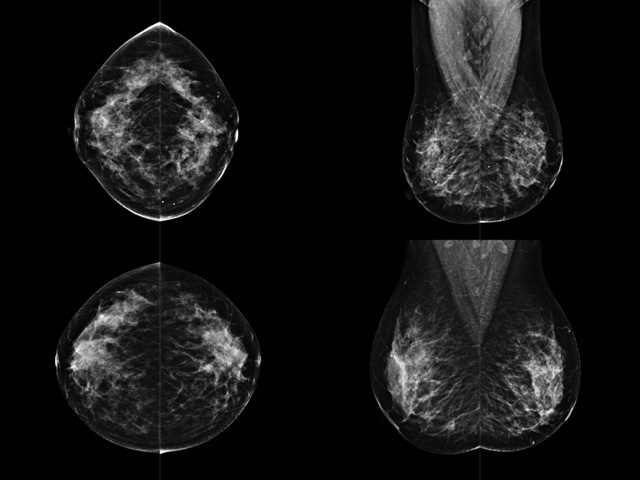

乳房檢查時候要注意一些細節,需要更深入的了解這樣才能使檢查更準確。乳腺DR是乳腺癌的篩查診斷工具設備。是乳房方面檢查的重要影像方法。它可以臨床檢查出早期的乳腺癌。可以判斷良性惡性。因為它可以檢查出早期的病變。對良性惡性檢查的準確率達到90%以上。發病高峰年齡為45歲到54歲。50歲檢查出來乳腺癌病患,可以讓死亡率下降3成。所以30-40歲女性每年做一次乳腺DR檢查。40歲以上就一年兩次。如果家族史有乳腺癌的30歲以下也需要做檢查。清晰顯示乳腺各層組織嚴重的乳腺增生,乳腺炎,乳腺外傷也建議1年檢查一次。極大提高了早期乳腺癌的敏感度和診斷率。

大角度、高質量的乳腺檢查,可以讓女性帶來身體健康安全。為醫生提供了高清影像數據。乳腺檢查時候各個部位影像顯示出來。白色乳腺導管跟纖維結締組織。模糊的是脂肪。病變一般是不透明的白色。有需要放大來檢查。乳腺DR沒有重疊偽影。輻射劑量更少。因為乳腺癌發病每年都有所提高,對女性都造成了嚴重的身體健康危害。早做檢查早治療是不可忽視的舉措??梢源蟠蟮慕档?/span>死亡率。保證身體健康。一般檢查避開經期,來完7天左右是最佳的檢查時間。絕經的女性就沒有要求。孕婦不參加乳腺DR檢查, 6個月內準備妊娠的婦女也不宜行此檢查。